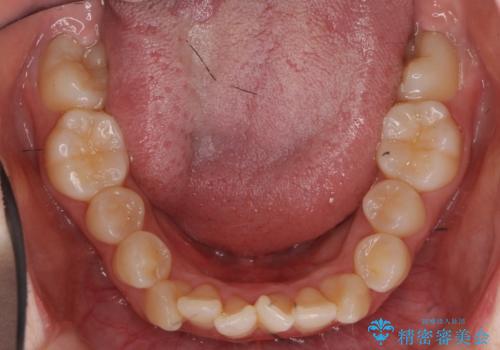

前歯は重度のがたつき、また奥歯はすれ違っていました。

上下左右4本抜歯の可能性を説明していましたが、実際は上顎2本の小臼歯抜歯で済みました。

上下の顎の幅もあっておらず、成人でしたが手術なしで上あごを骨から広げる処置(急速拡大装置)を行いました。